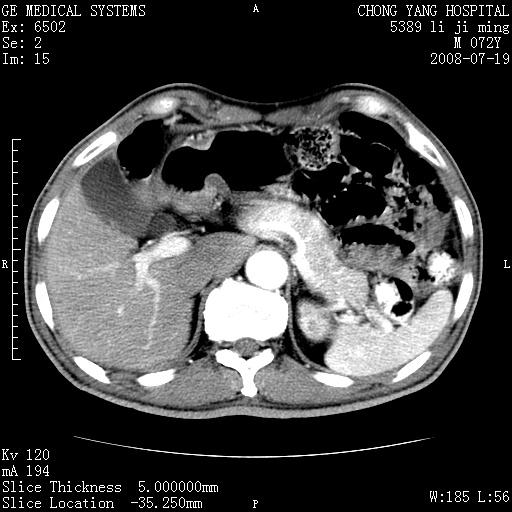

以下是引用zjzjr在2008-7-19 20:57:00的发言:[br]胰头增大,边缘模糊,周围可见渗出影,右侧肾前筋膜增厚.支持胰腺炎.

以下是引用yangyudong333在2008-7-20 6:56:00的发言:[br]胰腺增大尤以胰头明显,边缘模糊,周围可见渗出影,右侧肾前筋膜增厚,肠管於涨.支持胰腺炎

以下是引用不学无术在2008-7-19 23:15:00的发言:[br]胰腺增大尤以胰头明显,边缘模糊,周围可见渗出影,右侧肾前筋膜增厚,肠管於涨.支持胰腺炎